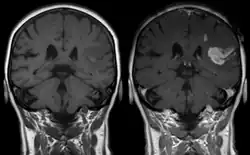

Effect of contrast agent on images: Defect of the blood–brain barrier after stroke shown in MRI. T1-weighted images, left image without, right image with contrast medium administration.

Gadolinium-based pharmaceuticals alter the relaxation time, and hence spectral line shape, of those protons that are in water molecules that are transiently attached to the paramagnetic atoms, resulting contrast enhancement of the MRI image.[12] This allows better visualisation of some brain tumours.[12]